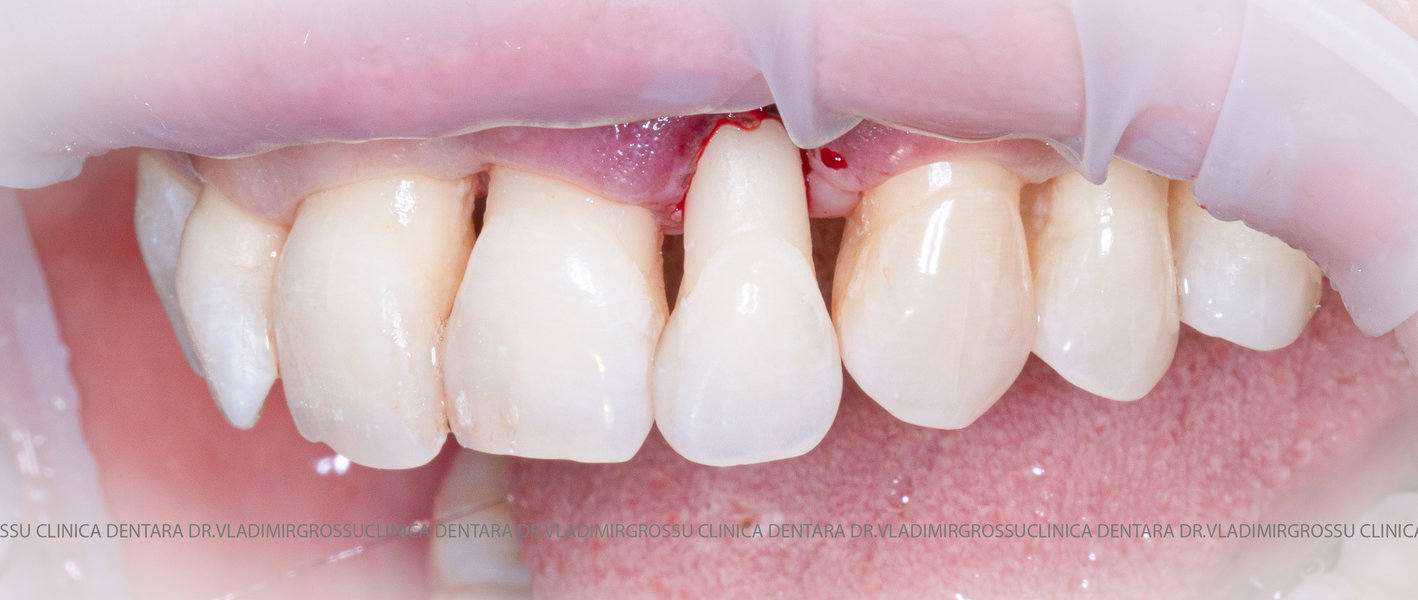

Adiția de gingie (gingivoplastia)

Aditia gingivală este o procedură chirurgicală ce corectează diverse probleme estetice și funcționale, cum ar fi recesiunea gingivală. În implantologia modernă, aditia de țesut moale este utilizată aproape în fiecare intervenție de inserție a implantului dentar pentru a asigura un aspect estetic natural și o bună integrare a implantului în cavitatea bucală.

Adiția osoasă are un rol crucial pentru poziționarea corectă și stabilă a implanturilor dentare. Clinica stomatologică Dr. Grossu din Chișinău promovează o abordare chirurgicală estetică și predictibilă, adaptată fiecărui caz în parte.

Medicii noștri au o vastă experiență atât în chirurgia estetică, cât și în protezarea cu un grad înalt de naturalitate, ceea ce ne permite să gestionăm cu succes și cele mai complexe cazuri.